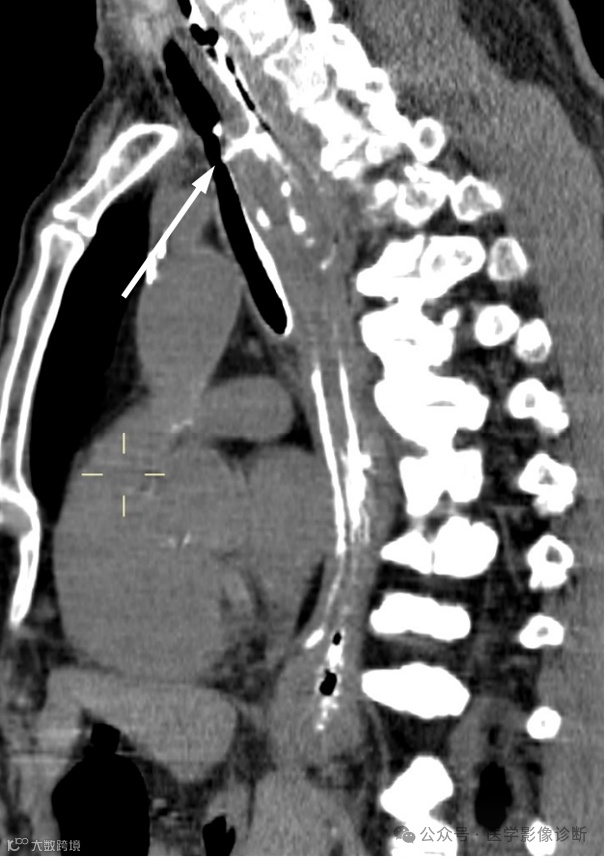

患者,男性,67岁,食管癌术后。

轴位 CT 显示食管癌术后变化(a, b)。然而,由于临床提供的申请表没有提醒,放射科医生只描述了术后变化,没有提及气管食管瘘。多平面成像(MPR)可以更好地显示瘘管。根据口服造影剂的使用情况,放射科医生应该明白医生想要观察是否发生了瘘管。